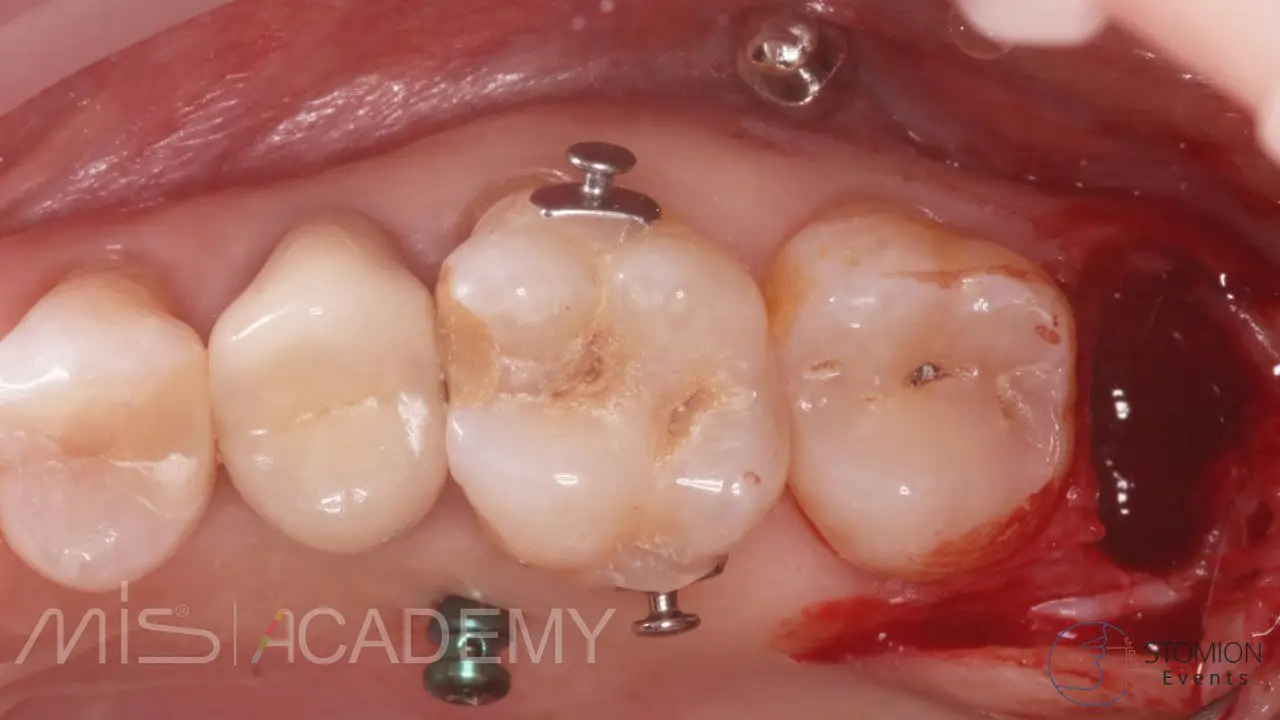

Диагноз: Адентия 4.6, мезиальный наклон 4.7, зубоальвеолярное выдвижение 1.6, перелом 3.6.

— 4.6 имплантация MIS C1 3,75х10 + connect 2мм + СТТ, фиксированный апикально к надкостнице, перекрыт расщепленным лоскутом.

— 3.7 удаление, одномоментная имплантация в перегородку, MIS C1 4,2×13 + connect 2мм, в лунки Bio-Oss S + A-PRF + немедленная нагрузка.